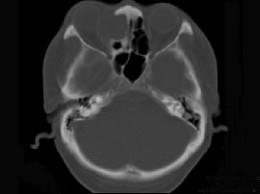

问题 女性38岁,右侧眼球运动障碍伴眼球突出4个多月,CT扫描如图,请选择正确的描述和答案 ( )

选项 A、考虑为右侧筛窦黏液囊肿 B、考虑为筛窦癌 C、囊性肿块向右侧眼眶内突入,压迫内直肌 D、右侧眶内壁呈受压变薄、断裂 E、右侧筛窦内可见囊性肿块影,边缘光整

答案 ACDE